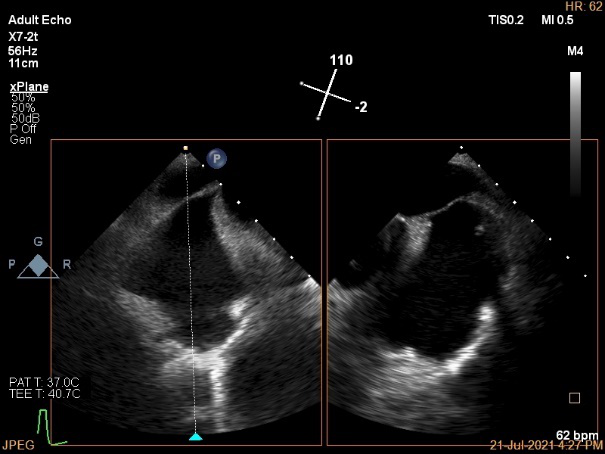

术前超声诊断:

长轴:左室下后壁节异,LAV:101ml,LVEDV:239ml

Bicom:MR(重度),返流束宽15.8mm,返流面积10.6cm²

PISA法定量EROA:0.69cm²,Rvol:168ml,RF:55%

肺静脉血流频谱呈收缩期反向

3D MV View

3D-color MV view:血流主要来源于2区近3区

Qlab软件勾画估测瓣口面积约:6.16cm²

二尖瓣口平均跨瓣压差:1mmHg

TEE Bicom返流量评估

TEE 4-Ch view返流量评估